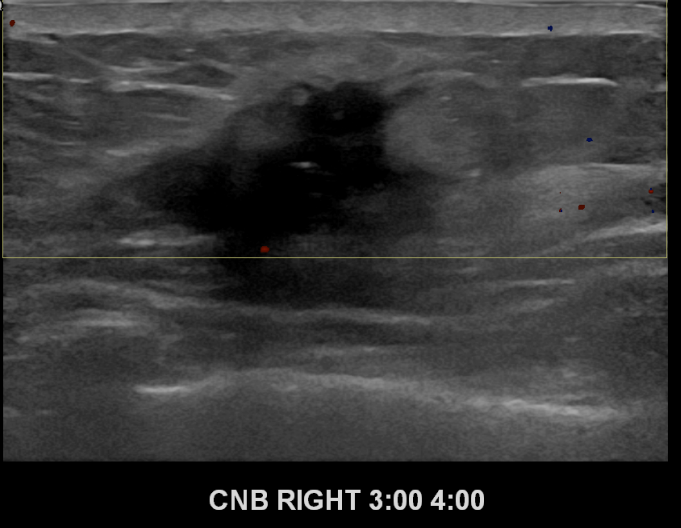

상기환자 우측유방에 딱딱한 멍울이만져져 내원하신 30대여성분으로 좌측유방의 혹 조직검사시행후 유방암 진단되었습니다